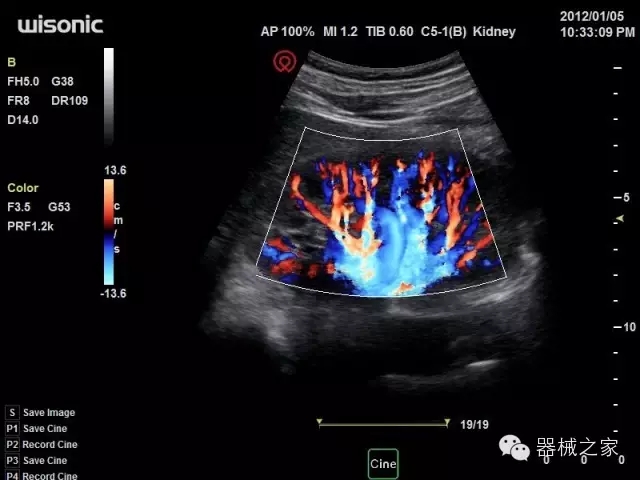

臨床圖片賞析

·智能微血流成像技術:智能微血流捕捉技術可以提取出隱藏在背景噪聲中的弱血流信號,大大提高低速血流的敏感性;

·移植S40高端臺式彩超高端平臺技術,滿足超聲科腹部、淺表、婦產(chǎn)科、心血管、肌骨等應用,提供超聲科完美解決方案;